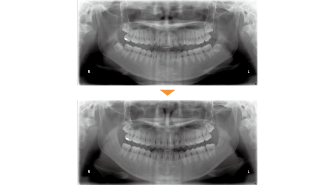

| 主訴 | 前歯の突出が気になる |

| 年齢・性別 | 28歳 / 男性 |

| 治療方針 | 上顎前突及び過蓋咬合。下顎の後退感が顕著なため、口元の突出感が目立つ。下顎前歯の1歯欠損と左側大臼歯に鋏状咬合がある。完全に突出感を改善するのは困難と思われるが、できる限り上顎前歯を後退させる。 ※治療後オトガイ部の緊張がとれて、プロファイルはある程度改善できた。 |

| 抜歯部位 | 上顎左右第1小臼歯、下顎前歯、左右第3大臼歯(親知らず) |

| 使用装置 | 歯科矯正用アンカースクリュー、マルチブラケット装置 |

| 治療期間 | 38か月 |

| リテーナー | 上顎インビジブル、下顎インビジブル |

| 費用 | 840,000円(税別) |